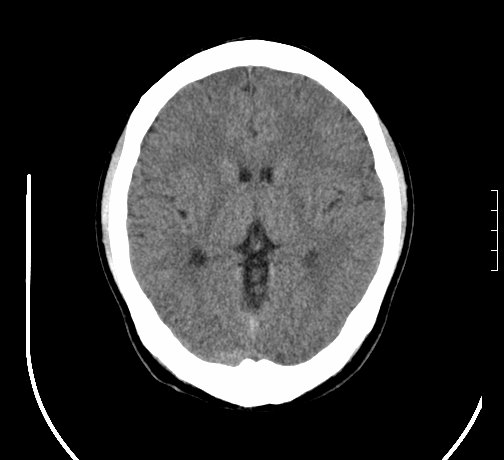

女,28岁,幼时有癫痫,常有发作,服药后可几月不发作,走路不稳3-4月,加重一月。

小脑发育畸形?

小脑萎缩。

考虑小脑发育不良,建议mri检查。

患者出现走路不稳是近几个月的事,而癫痫则有幼时就有,常发,则会常服药,癫痫药可引起小脑综合症,小脑萎缩,而小脑发育不良的主要症状不是癫痫

考虑癫痫,长期间断发服抗癫药,导致小脑综合症,小脑萎缩

考虑小脑发育不良伴小脑萎缩,建议mri检查。

小脑萎缩,原因待查,建议mri检查。